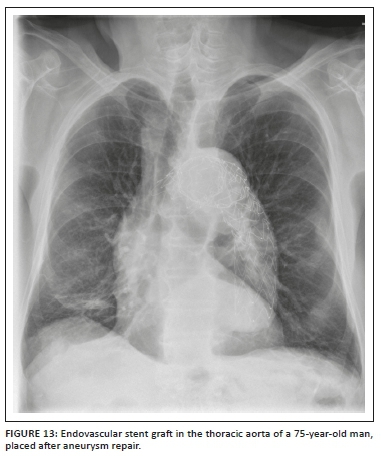

Medical devices and materials such as electrocardiogram (ECG) leads, ventilator tubing, syringes, clamps, temperature sensors, post-coronary artery bypass grafting (CABG) sternotomy wires, surgical clips, orthopaedic implants, gown snaps, etc. are commonly seen on CXRs. Because of its limited scope, we have not included cardiac devices in this article. However, there are other non-cardiac iatrogenic objects that can be seen on CXRs and these have been summarised in Table 2. Radiologists need to recognise them, be aware of their function and look for any related complications.